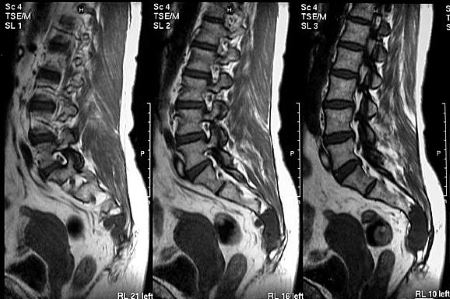

Опухоль на МРТ.

Нередко причиной болезненности копчика становится спондилолистез. Он развивается в результате травмы, дегенеративных изменений позвоночника, опухолей, когда смещается вышележащий позвонок по отношению к нижележащему.

Спондилолистез на МРТ.

МРТ, УЗИ

С помощью УЗИ можно диагностировать патологии опорно-двигательного аппарата на ранней стадии развития. Исследование проводится для оценки состояния кровеносных сосудов, расположенных около копчика и в органах малого таза. УЗИ — самая безопасная диагностическая процедура, позволяющая с высокой точностью обнаружить опухоли и воспалительные процессы в брюшной полости.

На полученных при МРТ изображениях отчетливо визуализируются мягкие, хрящевые, костные структуры. Диагностическая манипуляция часто используется при неинформативности других процедур.